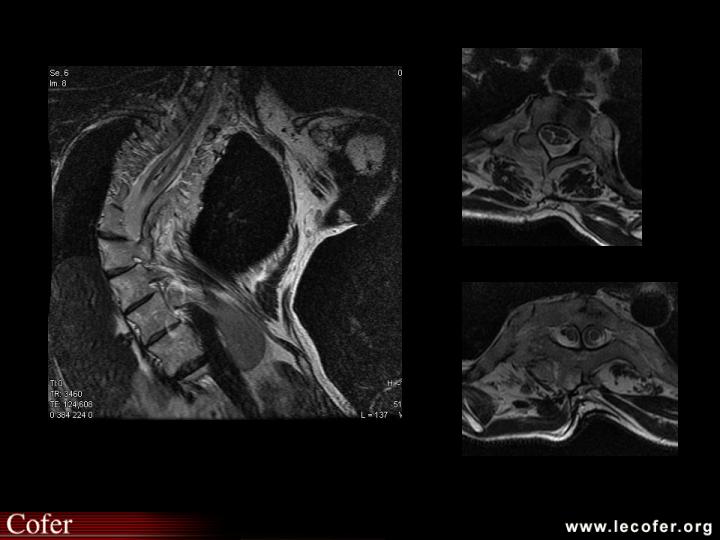

Pied diabétique : ostéoarthropathie neurogène : dislocation de l'arrière-pied.